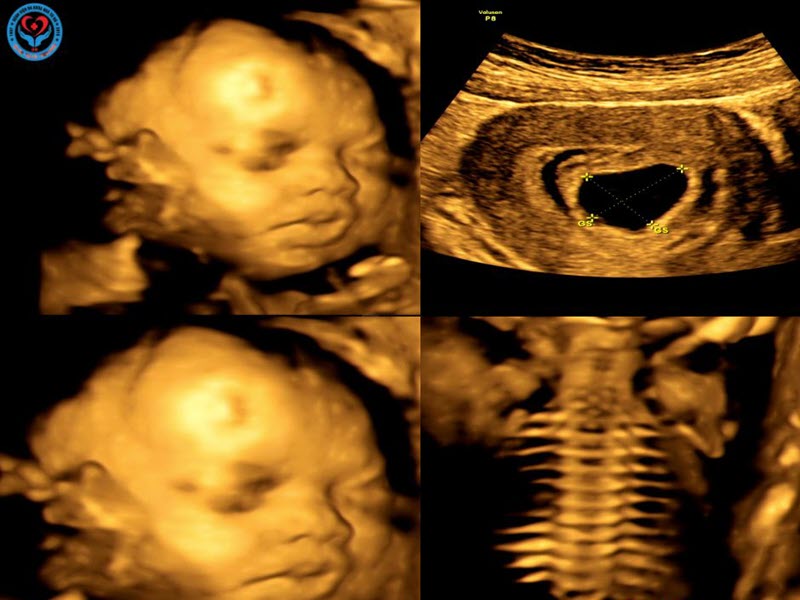

- Bệnh viện được trang bị máy siêu âm 2D, 3D, 4D và Doppler màu thế hệ mới.

- Hình ảnh rõ nét, chân thực, hỗ trợ phát hiện sớm các bất thường nhỏ nhất của thai nhi.

- Giúp mẹ bầu có trải nghiệm thú vị khi được nhìn thấy hình ảnh bé cử động, mỉm cười, mút tay ngay từ trong bụng.

- Máy siêu âm 4D hiện đại, hình ảnh sắc nét, rõ ràng.